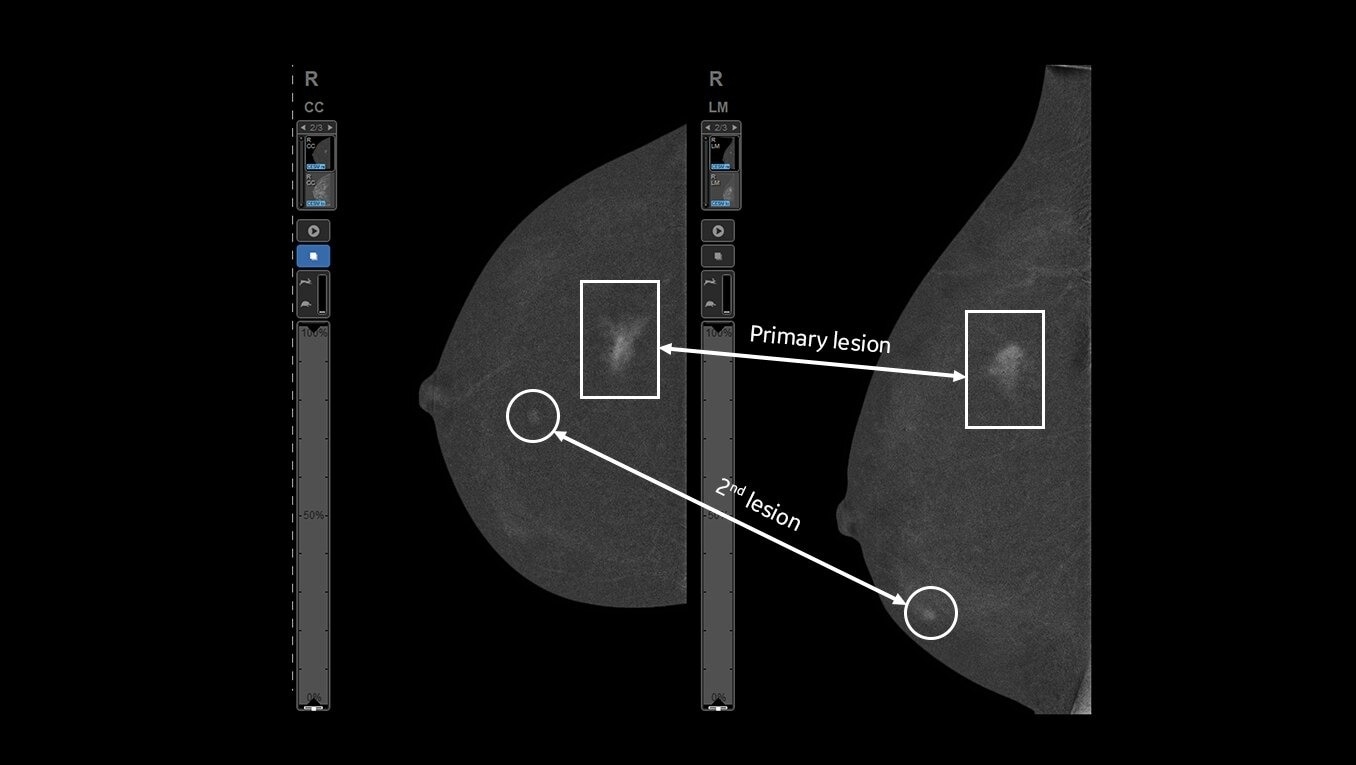

Fast procedure

CEM biopsy can be done within 15 minutes1.

Efficient

Switch to interventional on the same system within your current room in 2 minutes4.